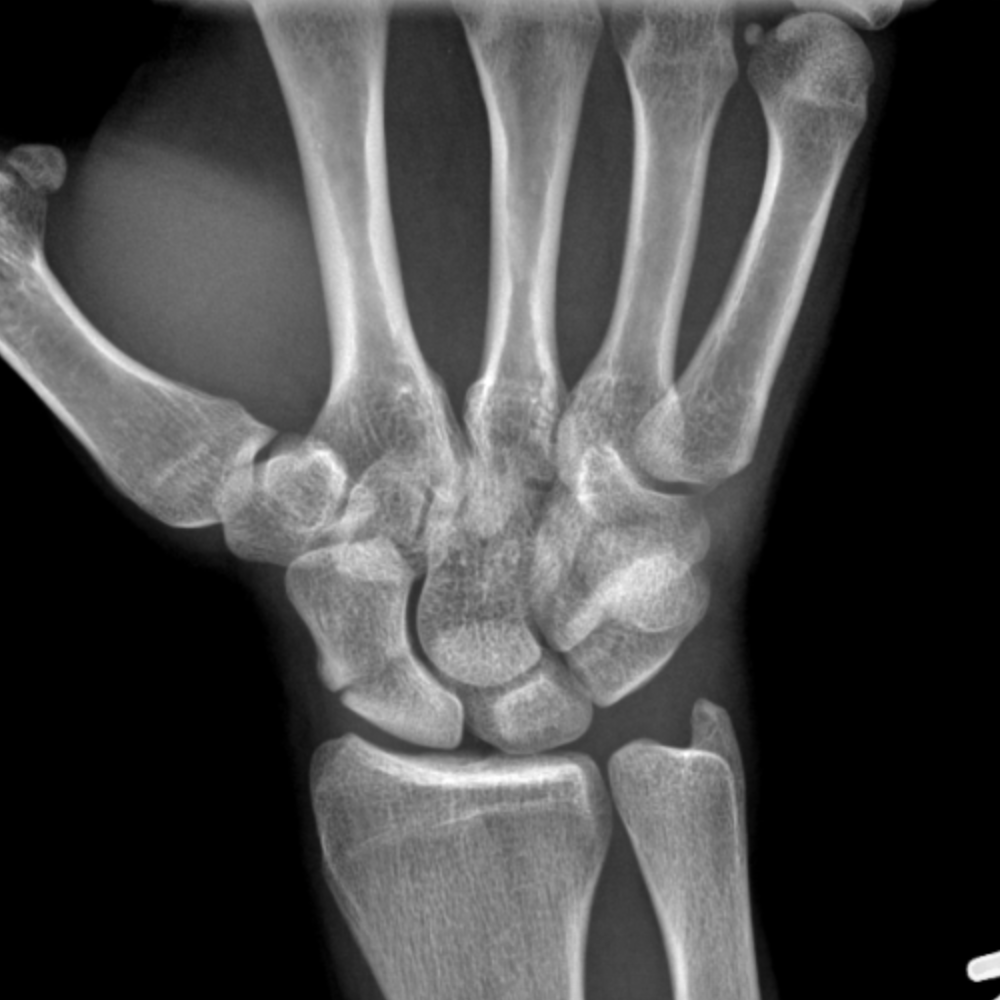

Fractures through the scaphoid bone) are common, in some instances can be difficult to diagnose, and can result in significant functional impairment. Performing rehabilitation exercises after suffering a scaphoid fracture can help you retain full function and mobility in your wrist.

Of (2a) despite immobilization, a fracture line through the scaphoid waist (arrow) remains visible. If the scaphoid fracture is not showing enough evidence of healing, rom may be delayed. Symptoms can include pain and swelling around the wrist. Scaphoid fractures can be mistaken for wrist sprains because they have similar symptoms. A delay in the diagnosis and treatment of a scaphoid fracture may alter the prognosis for union, increase the risk of avascular necrosis, and. Distal radius fractures programme online course: Scaphoid fractures most often occur in males between the ages of 15 to 30 years old and usually are sustained with wrist hyperextension and radial deviation as a individuals with a scaphoid fracture often present with pain, swelling, decreased range of motion, and tenderness in the anatomic snuffbox. Frequently, however, the diagnosis of this scaphoid injury is delayed; Rehab and return to sport treatment of acute scaphoid fracture in the athlete depends on: Scaphoid fracture | faqs answered. A scaphoid fracture is the most common type of carpal fracture affecting young active people. By dr arun pal singh. Treatment may involve surgery to prevent the risk of nonunion. A scaphoid fracture is an injury to one of the small bones in the wrist. The scaphoid bone is a small bone located at the base of the thumb next to the radius, one of the bones in the lower arm. A scaphoid fracture is a type of wrist fracture that occurs most commonly from a fall on the outstretched hand. Scaphoid fractures are an important public health problem as they predominantly affect.